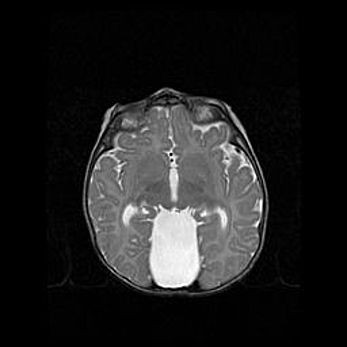

Множественные кисты обоих полушарий головного мозга, наибольшая из них в правой затылочной области. Ассиметричная атрофическая гидроцефалия.

Возраст: 7 месяцев

Вес: 5660 г

Пол: мужской

Окружность головы: 41,5 см

Срок гестации: 28-29 недель

Кисты головного мозга развиваются в результате многоочаговых некрозов вещества мозга и возникают вследствие перенесенной перинатальной инфекции, менингитов, энцефалитов, асфиксии, родовой травмы, расстройств мозгового кровообращения различного генеза. Образованию кист в веществе головного мозга плодов и новорожденных способствуют такие факторы, как высокое содержание в нем воды, недостаточная (или отсутствие) миелинизация и слабая астроглиальная реакция на повреждение.

Кисты могут сочетаться с гидроцефалией и другими поражениями головного мозга.